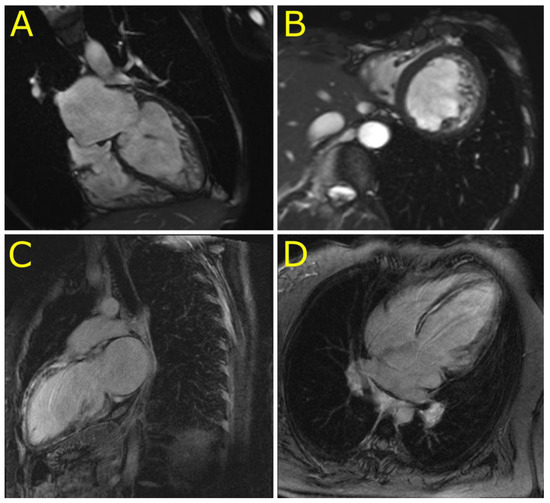

4.2. Novel Cardiac Phenotypes of Desminopathy